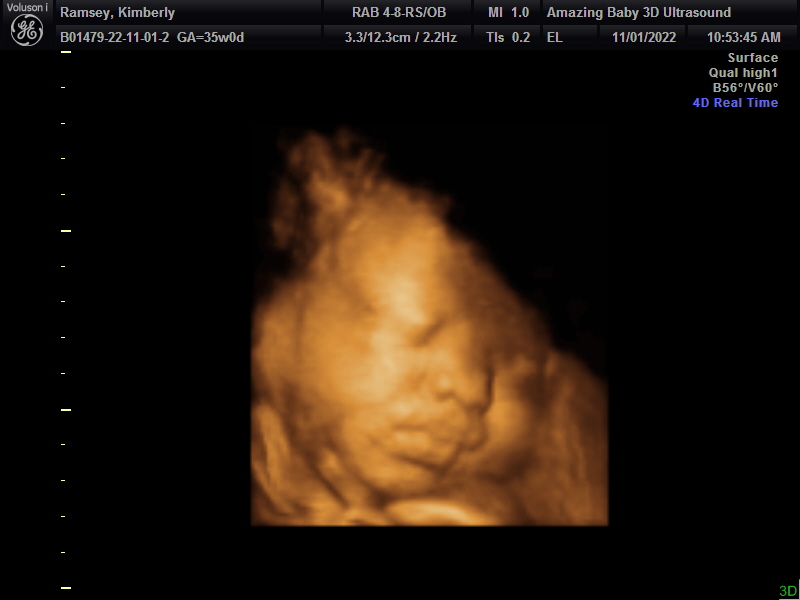

35 Week Ultrasound: Nov 1st, 2022

Anyways, once we did that, we started seeing our midwife and decided to do one more ultrasound just for fun before the baby comes.

The ultrasound technician told us Baby Shin had a full head of hair and was weighing in at 6lbs 11ounces! She also confirmed that baby was in an ROA (head down) position which was great news since I was striving for a natural, vaginal birth.